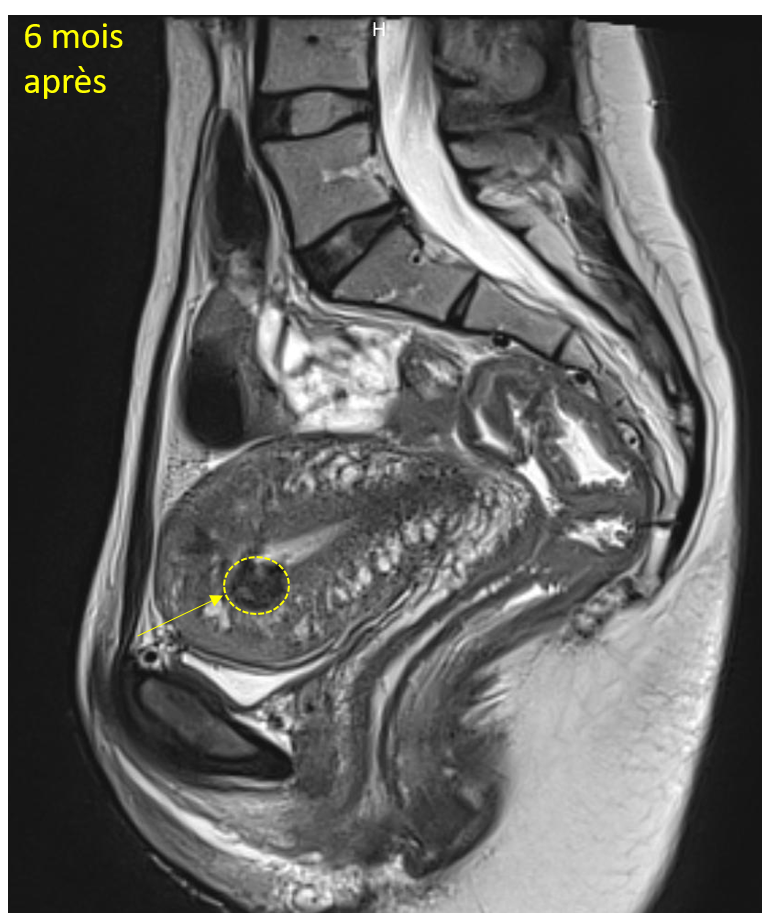

Les études montrent que la plupart des patientes voient leurs symptômes s’améliorer significativement dans les mois suivant l’intervention, avec une réduction durable de la taille des fibromes (diminution de leur volume > 70% en moyenne).

Une consultation de suivi de radiologie interventionnelle et une IRM sont programmées de manière systématique à 6 mois pour évaluer l’évolution de la taille des fibromes et s’assurer que l’embolisation a été efficace cliniquement.